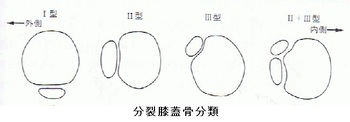

有痛性分裂膝蓋骨は、お皿の(膝蓋)骨が2つもしくはそれ以上に分裂していて、運動時や分裂部を

叩いて痛みがある場合をそう呼びます。

男子はお皿の骨の上外側部に分裂部があり、Ⅲ型と判明しました(下の分類図をご参照ください)。

分裂膝蓋骨の原因は小中学生の成長期に激しいスポーツをしていると、繰り返しお皿の骨に負担が

掛かり、分裂してしまう説や成長期の骨癒合不全という説もあります。